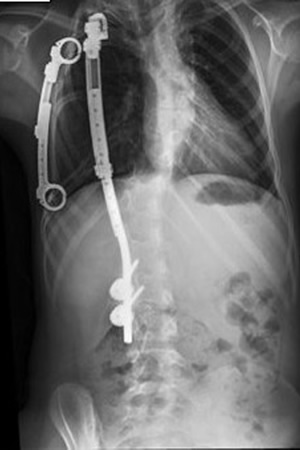

Grafilerle Skolyoz